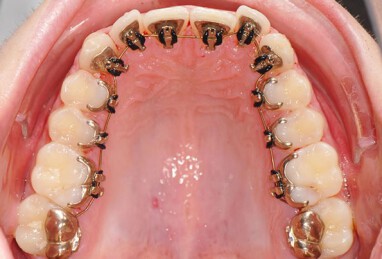

براکت لینگوال که در پشت دندانها قرار میگیرد، آزاردهندگی بیشتری برای کام و زبان شما ایجاد میکنند. هم چنین تمیز کردن و پاکسازی دندانها با حضور براکت لینگوال بسیار دشوارتر و ریسک پوسیدگی دندانها بیشتر خواهد شد.

ارتودنسی لینگوال